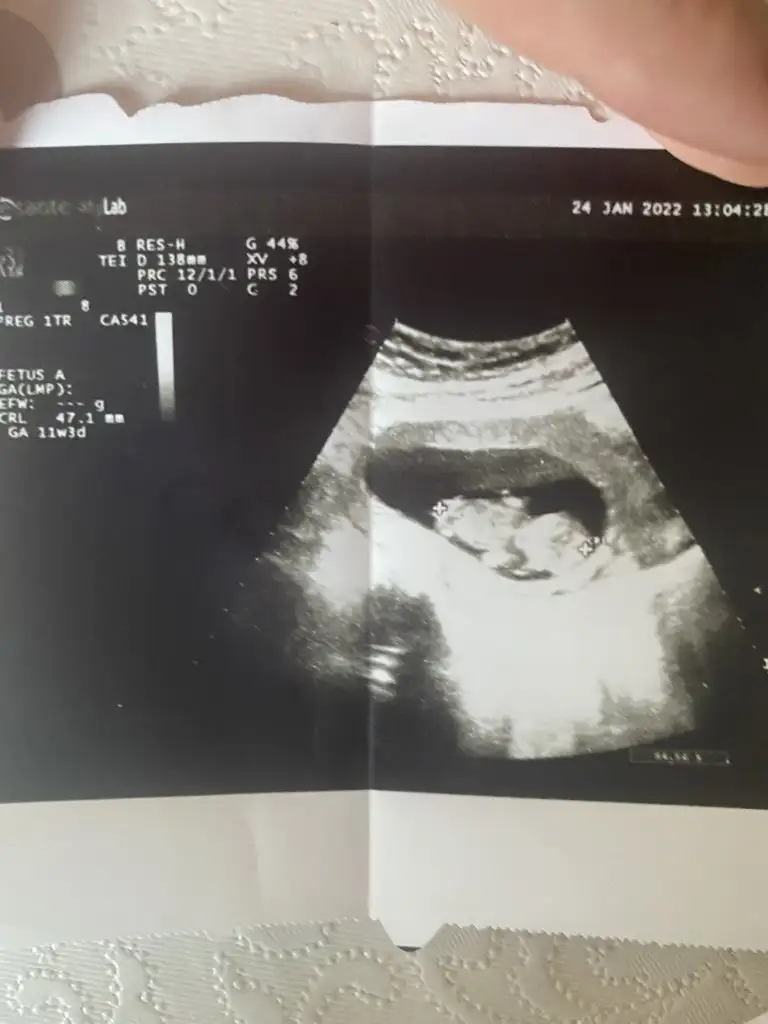

Merhaba. Rica etsem banada bir tahmin yapa bilirmisiniz?11+3dük bu fotoda Eki Görüntüle 3001346 Eki Görüntüle 3001345

Kız görünüyor

Seni varya pamuklara sarar sarmalarim kadinnnnm ağzın bal yesinKız görünüyor